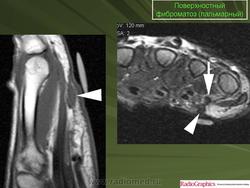

Пальмарный фиброматоз.

Пальмарный фиброматоз имеет вид инфильтрирующего и узловатого образования, исходящего из ладонного апоневроза и приводящего к контрактуре IV, V и, реже, других пальцев кисти. Может сочетаться с плантарным фнброматозом и болезнью Пейронье. Выделяют 3 стадии болезни пролиферативную, характеризующуюся беспорядочной пролиферацией фибробластов с образованием мягких богатых клетками множественных узелков с небольшим количеством коллагеновых волокон и скоплением аморфного межуточного вещества, инволютивную, отличающуюся упорядоченным расположением фибробластов, уменьшением числа клеток, нарастанием массы коллагена, началом сморщивания, резидуальную, при которой образуются плотные тяжи, напоминающие сухожилия. Отмечаются рецидивы после операций, метастазов не описано.